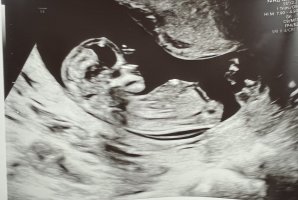

Ser ikke nub, men pga. hodeskalleform tenker jeg gutt. Dette er kun basert på info jeg har hentet på nettet da jeg desperat prøvde finne bevis på at jeg hadde fått opplyst riktig kjønn på UL altså. Hodeskalleform er visst en kjønnsgreie også. Jenter er visst runnere i panna(?).

Når du sier det , så stemte det litt med hodeform på mine tre . Rund på jentene og mer spiss på gutten .

Til ts , har ikke sjans å se noe tissefant :p